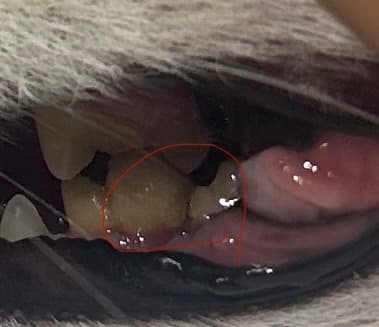

좌측 하악 어금니 파절로 병원갔더니

우측 하악 어금니도 깨져있다고 하네요

좌측은 이미 뿌리만있어서 발치확정이고

우측은 깨져있지만 턱이 떨리지도 않고 잘 씹고있는 상태인데 동네병원에선 양측 발치를 권하더라구요

말씀해주신 상황을 정리하면, 좌측 하악 어금니는 치관이 다 깨지고 뿌리만 남은 상태라 발치가 꼭 필요합니다. 반면 우측 하악 어금니는 파절은 있지만 겉보기에 잘 씹고 있고 턱도 떨지 않아 보호자님께서 바로 발치를 해야 하나 고민하시는 상황입니다.